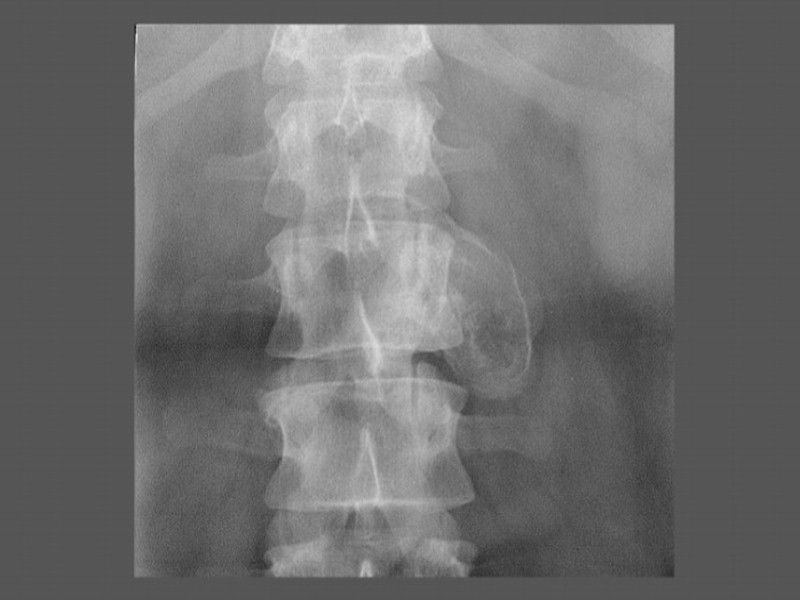

Гемангиома 1% от всех доброкачественных костных опухолей Выявляется чаще в пожилом возрасте Одиночная либо множественная Преимущественная локализация – тела Th8 – L5 позвонков, реже - лобная и височная кости, ребра Выглядит как вертикальная (реже горизонтальная) исчерченность тела позвонка, может быть легкое бочонкообразное вздутие. При других локализациях – очаг вздутия с разрушением кортикального слоя, веерообразно расходящиеся трабекулы, четкий склерзированный контур Может осложняться компрессионным переломом Малигнизируется редко